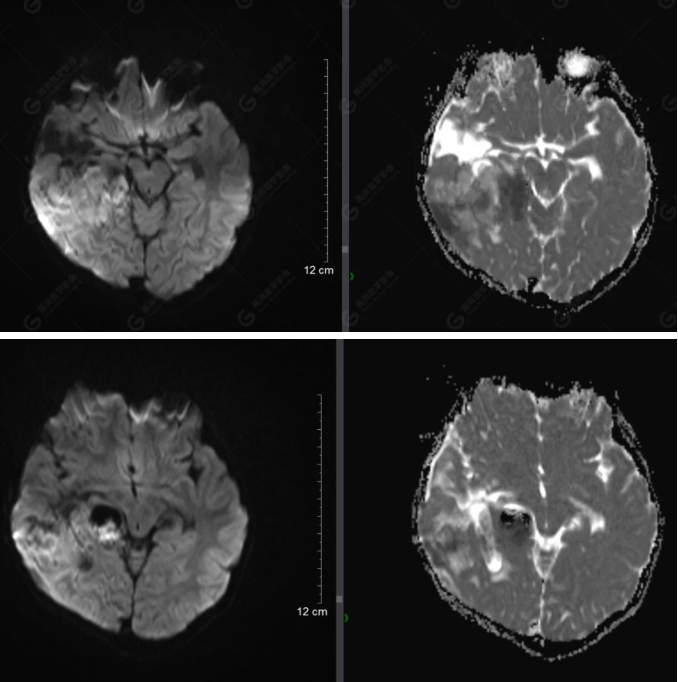

右側(cè)顳葉腫瘤切除術(shù)后(具體不詳):右側(cè)顳部骨質(zhì)不連續(xù)呈術(shù)后改變,右側(cè)顳葉術(shù)區(qū)見(jiàn)片狀長(zhǎng)T1長(zhǎng)T2信號(hào)影,F(xiàn)LAIR呈低信號(hào);術(shù)區(qū)后方右側(cè)顳枕葉見(jiàn)一巨大占位性病變影,邊界欠清,大小約6.2×5.8×4.3cm(前后×左右×上下),信號(hào)不均勻,T1WI呈等稍低信號(hào)間雜少許高信號(hào),T2WI呈高稍低混雜信號(hào),DWI示部分病灶彌散受限,相應(yīng)ADC圖減低,磁敏感序列見(jiàn)部分呈極低信號(hào),增強(qiáng)掃描可見(jiàn)明顯不均勻強(qiáng)化,鄰近硬腦膜及小腦幕增厚并明顯強(qiáng)化;另延髓右前方及右側(cè)橋小腦角區(qū)見(jiàn)一不規(guī)則形異常信號(hào)影,大小約3.2×1.3×3.7cm(左右×前后×上下),呈長(zhǎng)T1稍長(zhǎng)T2信號(hào),F(xiàn)LAIR呈等信號(hào),DWI未見(jiàn)受限,增強(qiáng)后明顯均勻強(qiáng)化,鄰近腦膜明顯強(qiáng)化。鄰近腦實(shí)質(zhì)及右側(cè)顳角明顯受壓;左側(cè)大腦半球未見(jiàn)局灶性信號(hào)異常,中線結(jié)構(gòu)稍左移。

非典型畸胎樣/橫紋肌樣瘤(AT/RT) 是一種高度惡性中樞神經(jīng)系統(tǒng)腫瘤,臨床罕見(jiàn),臨床表現(xiàn)無(wú)特異性,好發(fā)于 5 歲以下兒童,尤以 3 歲以下多見(jiàn),在兒童原發(fā)性中樞神經(jīng)系統(tǒng)(CNS)腫瘤中占 1%~3%。該腫瘤體積一般較大,幕上大于幕下,有明顯的占位效應(yīng)。該腫瘤成分復(fù)雜,囊變、出血、壞死常見(jiàn)。因此 AT/RT信號(hào)混雜,囊性部分呈 T1WI低、T2WI高信號(hào),增強(qiáng)后不強(qiáng)化;若瘤體出血,囊內(nèi)可見(jiàn)T1WI稍高信號(hào)、T2WI低信號(hào),實(shí)性部分在 T1WI上呈混雜等、低信號(hào),在T2WI 及 T2-FLAIR上呈混雜等高信號(hào),增強(qiáng)掃描后大部分呈環(huán)形條帶樣明顯強(qiáng)化,中心壞死區(qū)不強(qiáng)化。另外,該腫瘤實(shí)性成分在DWI上呈高信號(hào),說(shuō)明腫瘤細(xì)胞核密集,水分子擴(kuò)散明顯受限,提示該腫瘤惡性程度高,容易復(fù)發(fā)及轉(zhuǎn)移。